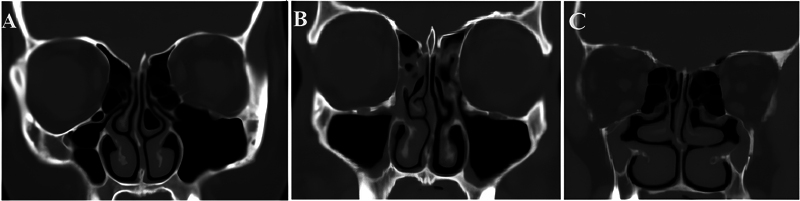

钩突(uncinate process, UP)是口鼻道复合体和中道中最重要和不变的标志。目的利用计算机断层扫描(CT)识别未发表的UP变异,并对其进行分类。方法对110例(220侧)旁鼻部CT进行扫描。轴向图像通过多平面重新格式化获得,以捕捉其他平面的精细细节。结果120例(220侧)CT扫描中,1型UP占84.5%,2型UP占12.3%,3型UP占3.2%,性别差异无统计学意义;中位UP占81.9%,垂直UP占16.3%,侧位UP占0.9%,缺失UP占0.9%,性别差异无统计学意义。总计8.63%的UPs采用了气动方式。结论本研究提高了外科医生和放射科医生对UP的认识,同时创建了一个标准的分类和描述,作为耳鼻喉科医生和放射科医生之间的共同语言,也可用于培训。

Introduction  The uncinate process (UP) is the most important and constant landmark in the ostiomeatal complex and the middle meatus. Objective  To identify the UP variations that have not been published before and establish a categorization using computed tomography (CT). Methods  The current study was carried out on 110 paranasal CT scans (220 sides). Axial images were acquired with multiplanar reformats to capture delicate details in other planes. Results  Out of 120 CT scans (220 sides), the UP was found to be of type 1 in 84.5%, type 2 in 12.3%, and type 3 in 3.2%, without significant diferences between genders, and it was found to be medialized in 81.9%, vertical in 16.3%, lateralized in 0.9%, and absent in 0.9%, without significant differences between genders. A total of 8.63% of the UPs were pneumatized. Conclusion  The present study improves surgeons' and radiologists' knowledge of the UP, while creating a standard classification and description to be used as a common language between otorhinolaryngologists and radiologists, which could also be used for training.